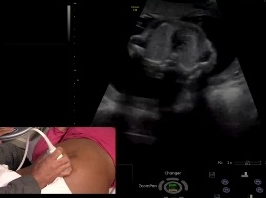

Quelques quizz en imagerie de l'abdomen

• Date : 20/06/2013